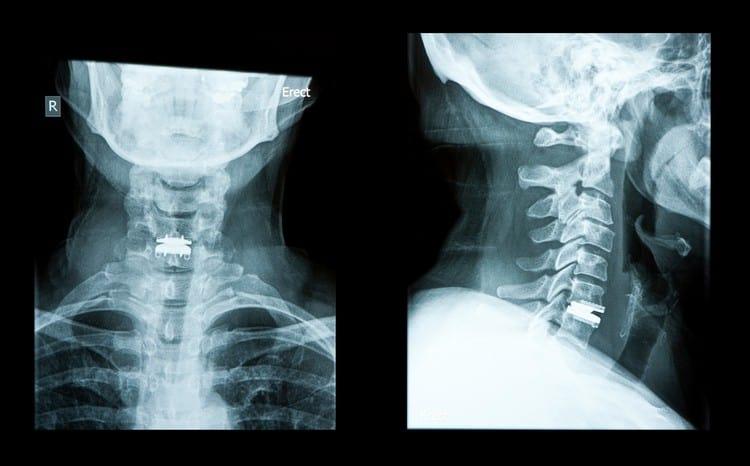

ကိုယ်ကာယစစ်ဆေးမှုတွေဖြင့် လည်းပင်းကျောရိုးမကြီးရောဂါကို စောလျင်စွာတွေ့ရှိနိုင်သလို ပုံရိပ်ဖော်ခြင်းနည်းပညာဖြင့် လည်းပင်းမှာဖြစ်နေတဲ့ ချို့ယွင်းမှုတွေကို အသေးစိတ်ရှာဖွေတွေ့ရှိနိုင်ပါတယ်။

– ဓါတ်မှန်။ ဓါတ်မှန်ရိုက်ခြင်းက လည်ပင်းပုံစံအသေးစိတ်ကို ပုံဖော်ပေးနိုင်ပြီး လည်းပင်းကျောရိုးမရောဂါ၊ အရိုးကျိုးခြင်း၊ အကျိတ်ထွက်ခြင်းနဲ့ ပိုးဝင်ခြင်းလိုမျိုး လည်ပင်းပြဿနာတွေကို ရှာဖွေတွေ့ရှိဖို့ ကူညီပေးနိုင်ပါတယ်။